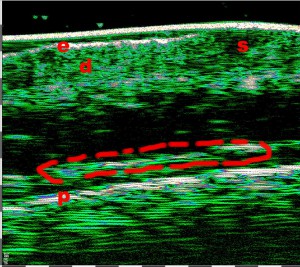

-Lifting με νήματα